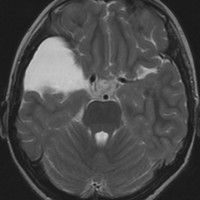

シルビウス裂くも膜のう胞,中頭蓋窩くも膜のう胞

前の例より少し大きいものです。1歳4ヶ月までは,のう胞が増大しましたがその後は同じ大きさで経過しました。